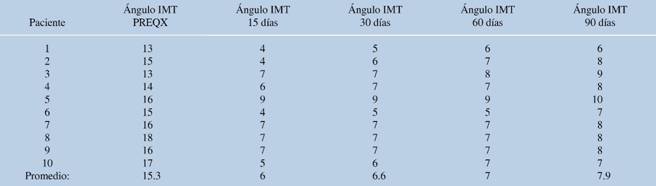

La corrección media del ángulo intermetatarsiano fue de 8.8 grados y la del ángulo metatarsofalángico, de 9.12 grados (inicial de 15 y 36.87 grados, respectivamente) (Tablas 2 y 3). Se presentó una complicación transoperatoria, con fractura diafisaria del segundo metatarsiano que se resolvió en el mismo evento mediante fijación con clavo Kirschner 1.6 mm. El análisis estadístico mostró una correlación inversamente proporcional de la corrección del ángulo intermetatarsiano y el puntaje de la escala AOFAS (p = 0.02).

Tabla 2: Resultados de la valoración del ángulo intermetatarsiano de acuerdo al tiempo de evolución.

Ángulo IMT = ángulo intermetatarsiano; PREQX = previo al tratamiento quirúrgico.